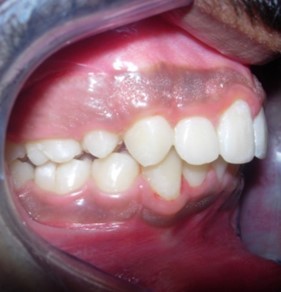

The soft tissue frontal and profile improved dramatically. (Figure 7a-b). The bilateral posterior crossbite was corrected. The severe increase in overjet of about 13mm was effectively reduced to 3mm and the severe deep bite was also corrected (Figure 7c,Figure 7d). Fixed maxillary and mandibular lingual retainers were given. (Figure 7e, Figure 7f). Post orthodontic treatment, normal root inclinations of the teeth and normal alveolar bone levels was observed. (Figure 8).

Figure 7c.Post-treatment intra-oral-Frontal

Figure 7d.Post treatment intra-oral – Right

Figure 7e.Post-treatment intra-oral-Upper occlusal

The end of treatment result showed a good improvement in the transverse, anteroposterior, and vertical dimensions with markedly improved dentofacial esthetics.

A combination therapy of a banded rapid palatal expansion appliance and orthodontic treatment with pre adjusted edgewise appliance therapy was instrumental in the correction of a severe skeletal Class II malocclusion with an orthognathic maxilla and retrognathic mandible. This two-phase therapy resulted in a dramatic improvement of the facial and smile esthetics with good occlusal interdigitation that enhanced the patient’s speech, personality and self-esteem.